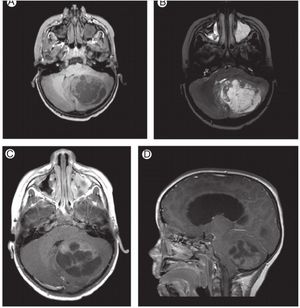

Juvenile polycystic astrocytoma